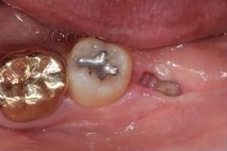

✅12일차 / 17일차

발치구멍이 아직 눈에 띄지만

시간이 갈수록 잇몸이 매끄러워지고

하얀조직도 잇몸으로 정상화되고 있습니다.

12일차 / 17일차